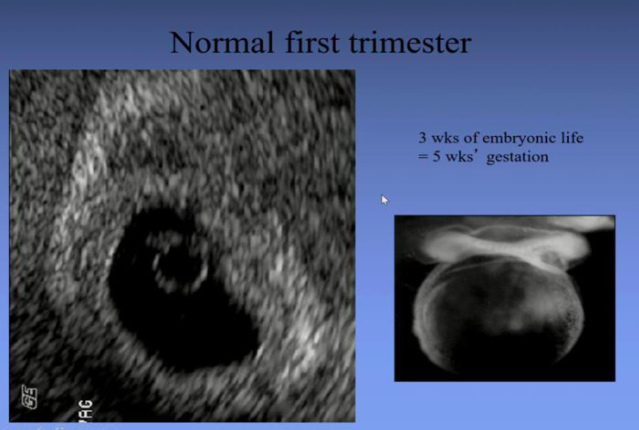

The embryo heart starts beating at age 5 when the embryo is still in the form of a disc

10 weeks gestation